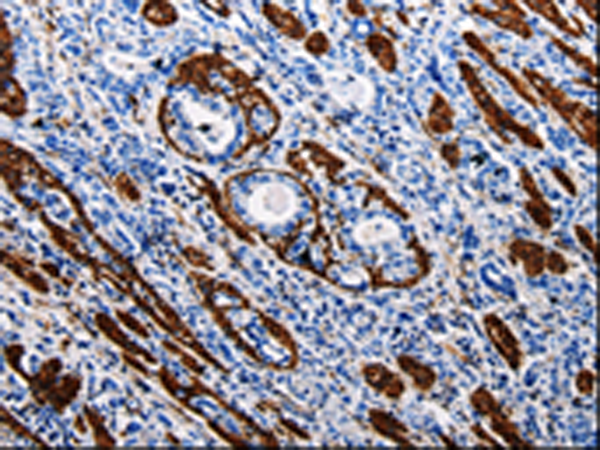

分类: 科研抗体货号: P10636别名: PI, A1A, AAT, PI1, A1AT, PRO2275, alpha1AT应用: WB,IHC反应种属: Human